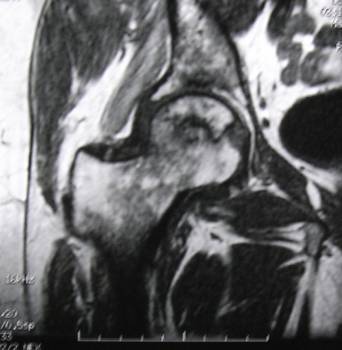

Avascular necrosis